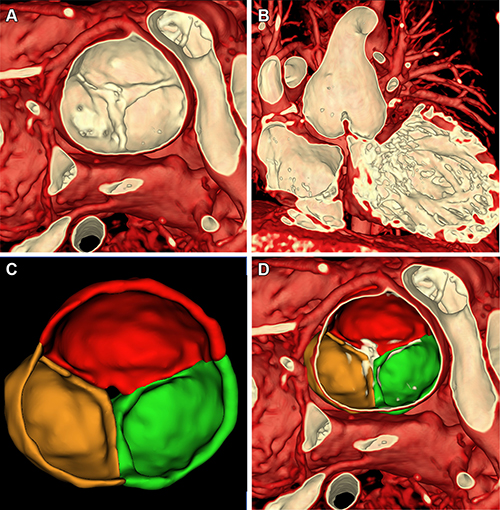

Figure 5. Volume rendering of multiphase steady-state imaging with contrast enhancement (ie, MUSIC) from ferumoxytol-enhanced cardiac MRI in a 4-year-old male patient with severe aortic insufficiency (patient 1) to inform valve repair. (A) Axial multiplane reconstruction in diastole. (B) Volume rendering from axial view in diastole. (C) Axial multiplane reconstruction in systole. (D) Axial view of volume-rendered image with cutting plane through aortic valve in systole.

Figure 6. Visualization of neoaortic valve using ferumoxytol-enhanced multiphase steady-state imaging with contrast enhancement (ie, MUSIC) cardiac MRI in a 5-year-old female patient with neoaortic insufficiency (patient 4) to inform valve repair. (A) Axial view of volume rendering looking down at neoaortic valve. (B) Coronal view of volume rendering cutting through aortic valve. (C) Segmentation of neoaortic valve demonstrates central defect. (D) Overlay of segmented image within volume-rendered image.